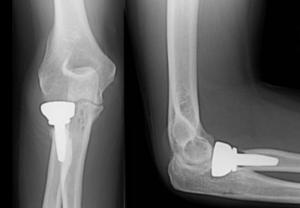

Radial Head Resection Arthroplasty Spacer

Flexible spacer used after radial head excision to prevent proximal radial migration and valgus instability.

Radial head resection arthroplasty involves the surgical removal of the damaged radial head. While this procedure can alleviate pain, simply removing the radial head can sometimes lead to long-term complications, such as proximal migration of the radius (the radius moving upwards towards the humerus), chronic wrist pain due to altered load distribution (Essex-Lopresti injury pattern), and elbow instability. To mitigate these risks and restore optimal elbow function, a "Radial Head Resection Arthroplasty Spacer" is often employed.

This specialized orthopedic implant is designed to replace the removed portion of the radial head. Its primary purpose is to maintain the correct anatomical relationship between the radius, ulna, and humerus, providing stability to the elbow and forearm while preserving the crucial rotational movements. The use of a spacer aims to reduce pain, improve joint mechanics, and facilitate a quicker, more effective return to function for patients. This guide will delve into the intricate details of these critical devices, from their sophisticated design to their profound impact on patient outcomes.